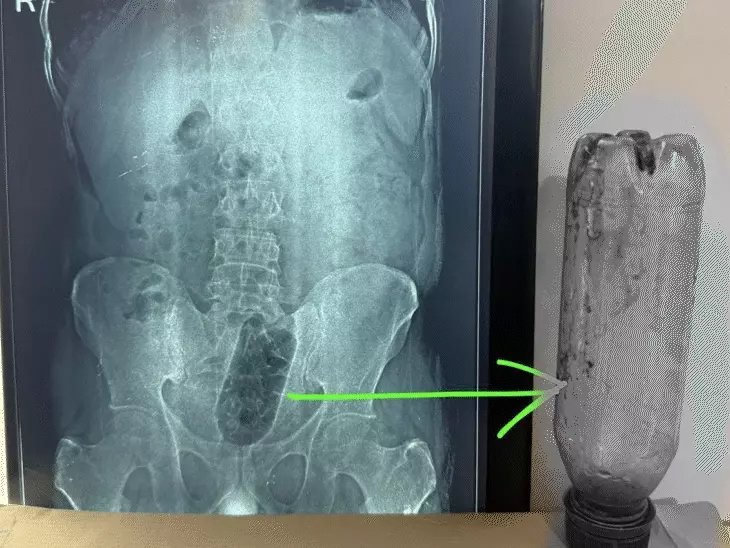

यहां डॉक्टरों ने युवक का एक्स-रे कराया तो मल द्वार के पास एक बोतल फंसी दिखाई दी। डॉक्टरों ने युवक को एडमिट करके इलाज शुरू किया। करीब एक घंटे के ऑपरेशन के बाद युवक को डिस्चार्ज किया गया। डॉक्टरों ने कहा-युवक साइको सेक्सुअल डिसआर्डर एनल एयरोटिसिस्म से पीड़ित है।

साकेत कालोनी में रहने वाला 38 साल के युवक शादीशुदा है। वह खुद का कारोबार करता है। युवक को असहनीय दर्द के चलते नवदीप हॉस्पिटल में मंगलवार को भर्ती कराया गया। डॉक्टरों ने तुरंत युवक का एक्सरे कराया। देखा कि मल द्वार के पास एक बोतल फंसी है।हास्पिटल के निदेशक वरिष्ठ सर्जन डॉ. सुनील शर्मा ने बताया कि युवक को तत्काल इमरजेंसी में भर्ती किया।

सर्जरी के दौरान ध्यान रखा गया कि बोतल को निकालते समय मलाशय फट न जाए और जख्म ना हों। करीब एक घंटे 10 मिनट में सर्जरी हुई। सर्जरी के बाद बोतल को बाहर निकाल लिया गया। सर्जन डॉ. सुनील शर्मा ने बताया कि ऑपरेशन करने वाली टीम में डॉ. दीपक , डॉ. भुवेश, राजेंद्र, गजेंद्र, शादाब और रोहतांग शामिल रहे।